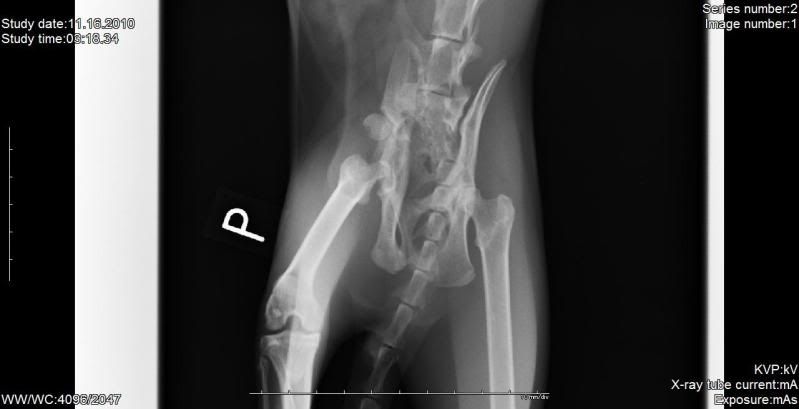

a co do Merlinka to myślę, że będzie ok bo on próbuje stawać na tej nodze, czasem się nią podpiera, ale zaraz cofa... wyraźnie widać, że boli, a jak boli znaczy że działa